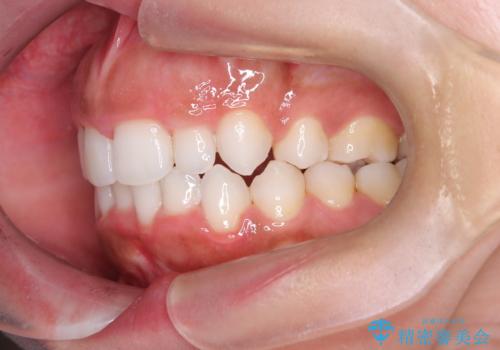

- 「前歯が出ていて並びも悪いのが気になる」との主訴で来院されました。診察の結果、上顎前歯の前突と中等度の叢生(ガタつき)が認められ、歯がきれいに並ぶスペースが不足していました。横顔のバランスと歯並びの両方を整えるため、上顎の左右の第一小臼歯2本を抜歯し、前歯を内側に下げながら歯列全体を整える治療計画を立てました。

患者さんのご希望もあり、取り外しが可能で目立ちにくいインビザライン(マウスピース矯正)を選択。抜歯スペースを活用しながら、叢生と前突感の改善を同時に目指しました。

治療はインビザラインによって進め、抜歯スペースを使って前歯を内側に引き込みながら、歯のガタつきも順に整えていきました。初期の段階で前歯の見た目が大きく変わり、患者さんにも「印象が柔らかくなった」と非常に喜んでいただけました。